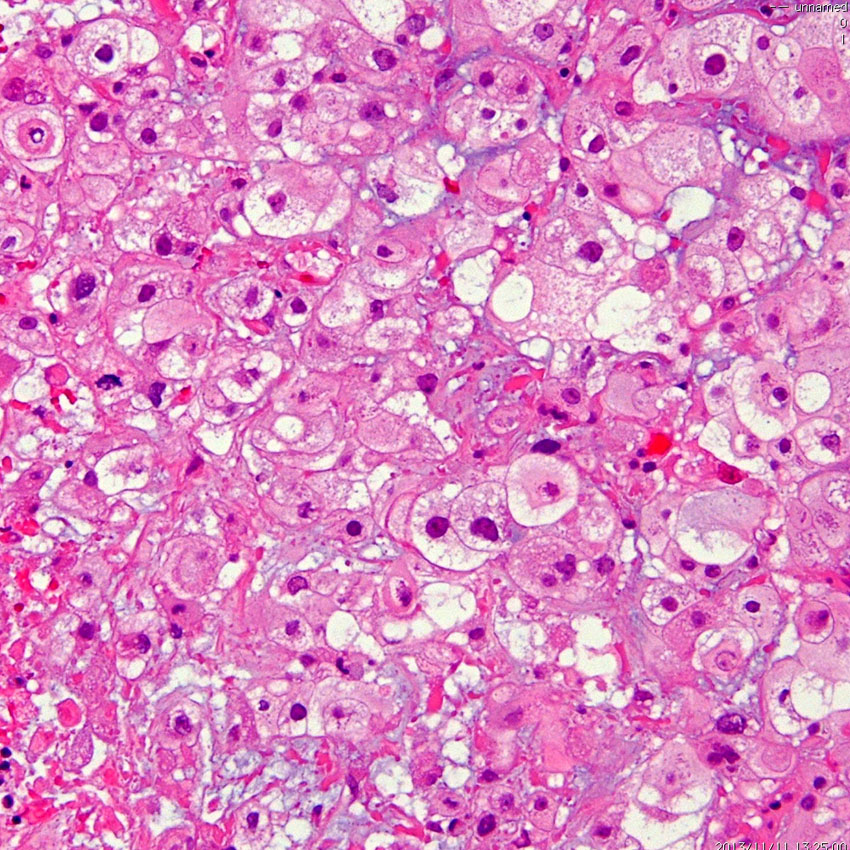

病理像です。軟骨様組織を混在しない純粋な脊索腫です。核を中心にして大きな丸い細胞体には空胞が目立ちます。空胞腫瘍細胞 physaliphorous cellsのシート状配列が特徴的です。左上の写真にわずかに粘液状間質(青く染まるところ)がみえます。